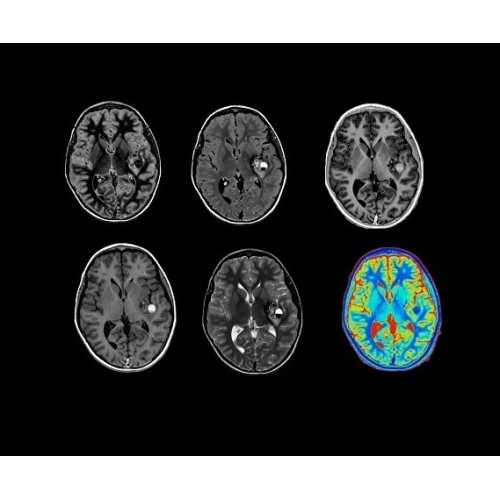

• HyperWorks — пакет програмных приложений, который включает технологию HyperSense для поразительной визуализации и скорости.

• ImageWorks — повысит производительность МРТ благодаря визуализации высокого качества с MAGIC, четкими результатами пост-процессинга с READYView.

Технология полной оцифровки изображения Total Digital Imaging (TDI) предлагает потрясающие достижения в области визуализации:

• Технология Direct Digital Interface (DDI)использует независимый аналого-цифровой преобразователь для оцифровки сигнала от каждого из 128 радиочастотных каналов, что обеспечивает значительное увеличение качества за счет уменьшения фонового шума.

• 48-канальная катушка TDI для головы, входящая в базовую комплектацию SIGNA Architect, обеспечивает феноменальную производительность с учетом особенностей каждого пациента. Благодаря гибкому и универсальному дизайну, высокому соотношению сигнал/шум и передовым технологиям визуализации, таким как HyperWorks, учитываются потребности подавляющего большинства пациентов.